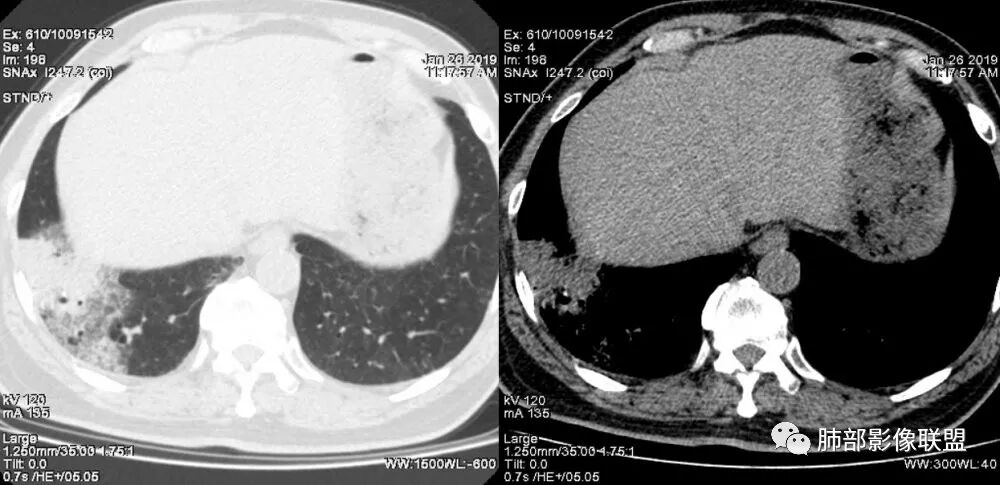

老年女性,右肺下叶沿胸膜下大片状高密度影,外周磨玻璃影,边界较清,内可见蜂窝征及支气管充气征,考虑肺炎型肺癌。

老年女性,咳嗽咳痰病史,右肺下叶大片磨玻璃实变影,胸膜下分布,支气管进入后扩张、僵直,磨玻璃影边界清楚,考虑粘液腺癌。鉴别肺炎。

中年女性,咳嗽咳痰。右肺下叶片状高密度影,部分实性密度,周围见边界清晰磨玻璃影,内见小空泡,实性区部分支气管堵塞,有重力效应,考虑肺炎型肺癌,建议查痰脱落细胞。

老年人,右肺下叶斑片状阴影,病灶有膨胀性,边缘可见磨玻璃影,其边界清晰,内见僵硬的支气管,部分支气管扩张,首先考虑占位性病变,粘液性腺癌可能。鉴别感染性病变,后者边缘多有收缩性改变或者平直,内部支气管走形自然。

老年女性,右下肺实变影,糊墙,外朝内发展,病灶里有小叶内间质增厚,周围边界清楚了GGO,支气管扩张明显,考虑粘液癌;不符合点,支气管扩张太厉害了,鉴别淋巴瘤。

患者中年女性,咳嗽咳痰就诊。胸部CT:右肺下叶后基底段片状实变影,由胸膜向内发展呈扇形,病灶里有小叶内间质增厚、蜂窝状影,周围边界清楚GGO,内可见扩张支气管,淋巴结无明显肿大。综合符合粘液腺癌。

1.本例病灶较大片混杂密度影,胸膜下分布为主(未沿着支气管分布),该分布特点可见于大叶性肺炎、干酪性肺炎、淋巴瘤及粘液腺癌等。可惜未提供增强扫描图像。

2.病灶示中央实变区,周围GGO,可见明显小叶间隔增厚,GGO边界清楚,应当考虑到恶性病变的可能性。肺炎因炎性水肿及渗出,影像上边界常模糊不清,注意早期粘液腺癌可出现似清非清的边界。粘液腺癌因粘液成份较多,密度一般偏低,纵隔窗病灶常会消隐或范围会明显缩小,这不同于炎性实变。

3.病灶内支气管走形略显僵直,侧支少(粘液阻塞),也符合肺腺癌的枯树枝征。而大叶性肺炎的支气管是管壁光整、通畅、自然,结核的支气管常常壁增厚,甚至狭窄后扩张;